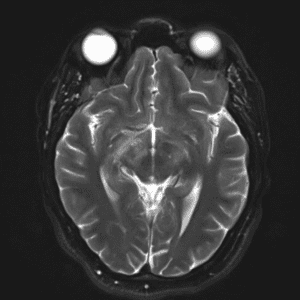

Case #2

Cavernous malformation